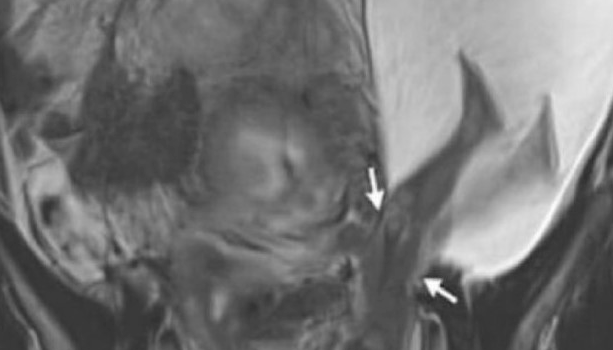

When she was at the 22nd week of pregnancy for an ultrasound examination, her attending doctor was completely astonished when he saw on the ultrasound how the little baby’s feet and legs were protruding through the amniotic sac.

This woman’s uterus was ruptured in one place, which allowed the child to get into this position.

This fascinating image, which captures the child as if it were trying to push the uterus out, went viral across the internet.